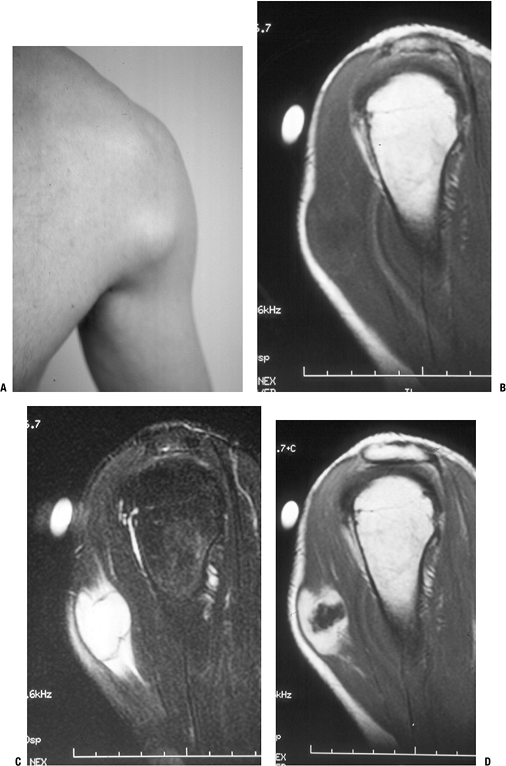

Figure 11-6 Nodular fasciitis of the shoulder. (A)

The patient presented with a 3-week history of a rapidly enlarging,

painful soft tissue mass over the anterior deltoid. Sagittal MR studies

show nonspecific findings of a heterogeneous intramuscular mass

hypointense to muscle on T1-weighted sequences (B), hyperintense on T2-weighted images (C), and enhancing on post-gadolinium sequences (D). -